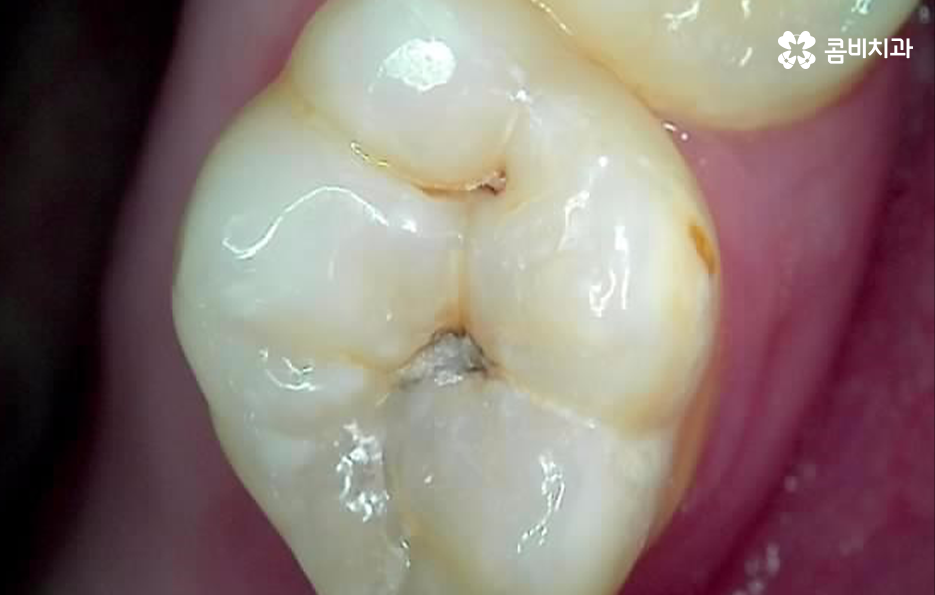

충치는 진행 단계에 따라 법랑질 충치와 상아질 충치, 신경조직의 충치, 뿌리 충치 이렇게 4단계로 구분할 수 있는데요. 쉽게 생각하면 치아의 구조로 볼 때 겉 부분을 이루는 법랑질부터 치아 안쪽으로 충치가 점점 깊어지고 심해지는 단계라고 이해하시면 될 거예요

충치 치료는 이처럼 진행 단계나 충치가 발생한 위치, 깊이 등에 따라 보통 레진, 인레이, 크라운 순서로 치료 방법이 달라지고 있는데요. 그중에서도 충치 신경치료의 경우 통증도 심하고 치료도 여러 진행되며 비용도 비싸다는 인식 때문에 신경치료를 일단 미루고 상태를 지켜보자고 생각하시는 분들도 있어요

충치 신경치료는 언제 하는지 대표적인 사례를 살펴보면 크게 두 가지로 구분할 수 있는데요. 충치가 신경조직에 근접하거나 침범한 경우 진행하는 신경치료가 있고 치아 뿌리 끝에 염증이나 고름 같은 게 생겨서 신경치료를 하는 경우가 있어요

우선 충치가 신경조직까지 진행된 경우를 먼저 살펴보면 신경에 도달한 충치는 보통 극심한 시림과 통증을 느끼게 할 거예요. 충치의 단계로 비교하자면 법랑질에 발생한 충치의 경우 별다른 증상을 못 느끼는 경우가 대부분인 반면에 신경에 충치가 도달하면 시림이나 통증이 매우 크다고 느낄 정도이며 심한 경우 일상생활이 어렵고 잠을 자기 어려울 정도로 불편함도 느낄 거예요. 그리고 간혹 선천적으로 신경이 뾰족한 경우가 있는데, 이 경우 신경이 노출되지 않아도 차가운 물을 먹을 때 시리거나 저작 시 통증이 발생할 수 있는데, 이 경우에도 신경치료 필요하고, 방치할 경우 신경이 변형되거나 죽으면서 뿌리 쪽에 염증이 생기는 경우가 있어요.